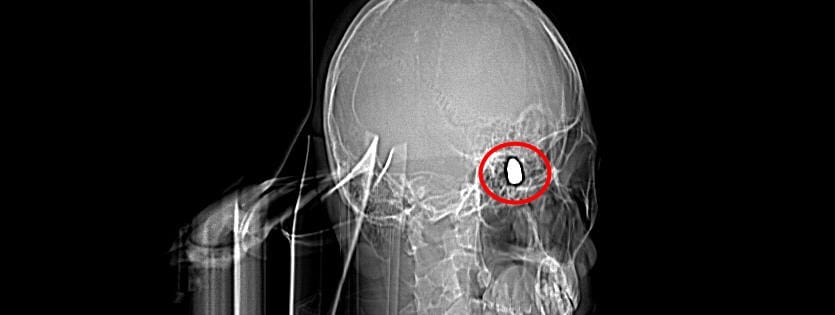

Çevredekilerin hastaneye götürdüğü Yusuf’un çekilen röntgeninde, başında mermi çekirdeği olduğu tespit edildi.

Doktorlar Yusuf'un başındaki merminin riskli bir bölgede olması sebebiyle çıkarılamayacağını söyledi. 4 gün yoğun bakım, 4 gün de serviste tedavi gören Yusuf düzenli olarak doktor kontrollerine gitti.